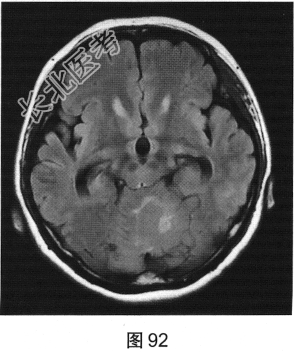

- 多项选择题2.[提示]患者行CT及MRI检查,如图90~图95所示。CT及MRI上的阳性影像学表现包括( )

A、MRI示右侧囊实性病变

B、病变实性成分增强扫描可见明显强化

C、MRI示左侧囊实性病变

D、MRI示右侧少许水肿

E、CT示左侧低密度灶

F、病变实性成分增强扫描未见明显强化

G、CT示右侧低密度灶

H、MRI示左侧少许水肿